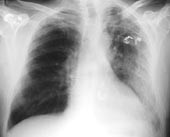

Pasient 1 . 50 år gammel tidligere frisk storrøykende kvinne, som hadde vært på 14 dagers reise på Cuba. Hun ble syk med feber, hodepine og muskelverk to dager før hjemreise. Dagen etter hjemkomst fikk hun vanntynne diareer, feber opp i 40 ˚C. Hun ble behandlet symptomatisk med loperamid, men ble innlagt i sykehus etter to dager pga. manglende behandlingseffekt. Ved innleggelse var hun afebril og normotensiv, men hadde hviledyspné. Røntgen thorax viste svær fortetning i venstre underlapp, CRP var 720 mg/l, leukocytter 9,4 × 10 9 /l, laktatdehydrogenase (LD) 877 U/l, natrium 134 mmol/l og det var lett forhøyede transaminaseverdier. Legionellaantigen i urin ble påvist dagen etter innkomst, og immunfluorescensundersøkelse av indusert sputum var positiv for legionellaantigen. Det kom imidlertid ingen oppvekst. Hun hadde delvis amnesi for reisen, og de første dagene av sykehusoppholdet var hun påfallende apatisk. Hun ble raskt bedre etter oppstart av behandling med erytromycin, men fikk forbigående hørselsnedsettelse, sannsynligvis pga. høydosert erytromycin intravenøst. Hun fortsatte med klaritromycin per os i en uke etter avslutning av en ukes intravenøs erytromycinbehandling. Det videre forløp var ukomplisert.Ved fornyet anamnese fortalte hun at hun på flyet hjem og i dagene deretter hadde følt seg så syk at hun var blitt likegyldig med alt, og mannen hadde måttet ta initiativ til legeundersøkelse.